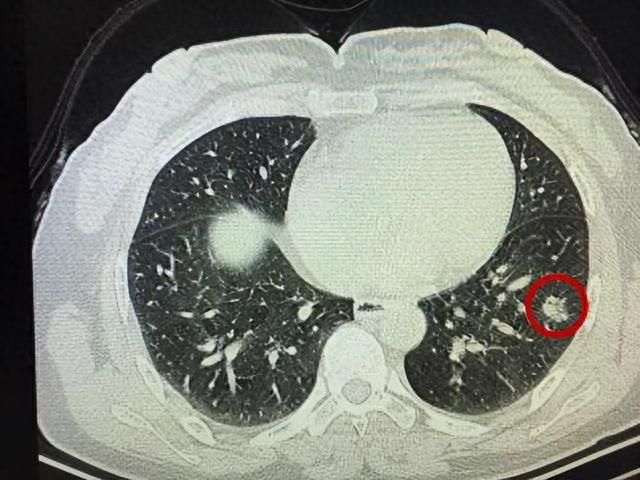

导语:肺结节这种问题属于是一种病因未明的多系统多器官的肉芽肿性疾病 , 经常会侵犯肺部、双侧肺、门淋巴结、皮肤以及眼睛等各项器官 , 其胸部受侵率能够高达80%~90%左右 。

在我们的日常生活当中 , 肺结节问题似乎变得越来越常见了 , 而且在临床上的检出率非常高 , 这种问题不仅会影响生活和工作 , 还有可能会给肺部带来不同程度的损伤 , 并且会容易增加肺癌发生 。

肺结节的病变率肺结节的病变率是指经过一定时间后 , 肺部结节发生癌变或恶化的概率 。

虽然肺结节病变率相对较高 , 但大部分肺结节是非癌性的 , 只有一小部分肺结节会发生恶变 。

根据相关研究和统计数据 , 肺结节病变率的范围在10%~20%之间 , 但需要注意的是 , 这一概率只是指在一定时间内的病变发生率 , 并不代表每个肺结节都会发生癌变 。

此外 , 良性的肺结节也有可能逐渐消失或保持稳定 , 而恶性的肺结节也有可能会被及时发现并进行治疗 。